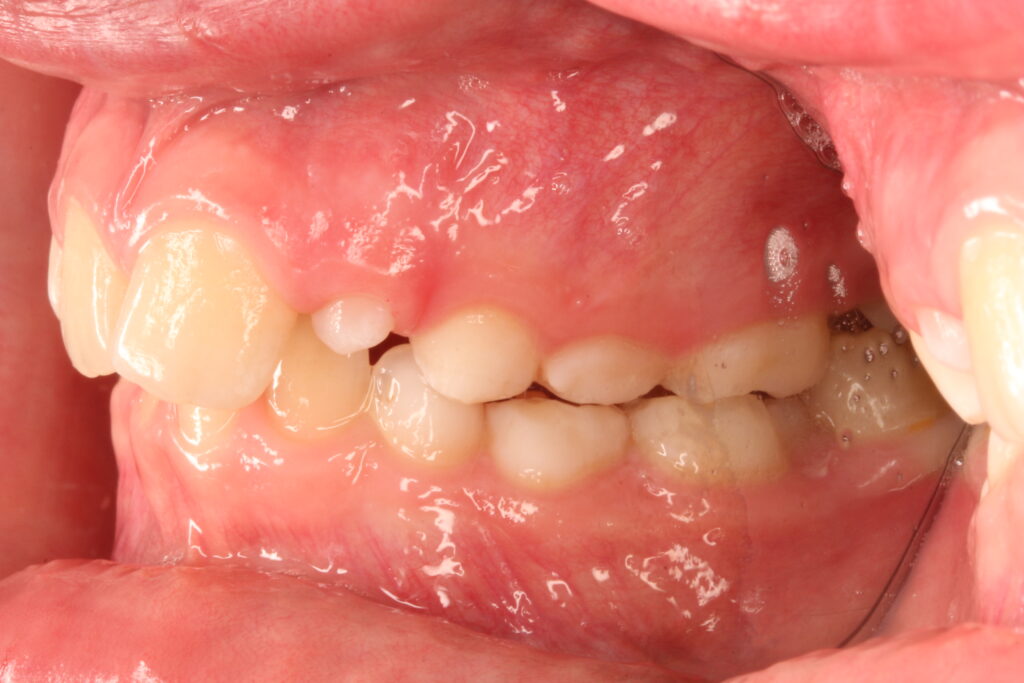

✔ Class II, Class III, aszimmetria és keresztharapás elméleti megközelítése

Az ALF készülék nem az agresszív erőhatásokra, hanem a funkcionális erők finom, biológiailag kíméletes irányítására épít. A klinikai tapasztalatok szerint ez tökéletes elég és mind a fogív fejlesztésében, keresztharapások megszűntetésében, helyteremtésben mind a nyelvtér növelésében jól működik.

A leggyakoribb a vegyes fogazat időszakában (6–11 év), de alkalmazható teljes tejfogazatban is nagyon korai kezelések esetében, akár 3-4 éves kortól is.